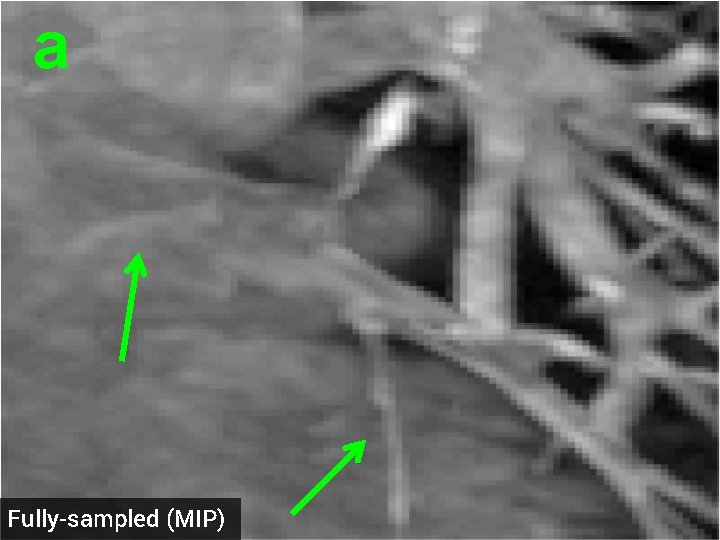

3 -D Compressed Sensing MRA § 512 x 76 voxel MRA dataset obtained from physiobank (see ref. [6]) § Simulated single coil acquisition § Retroactively undersampled at 1. 5 -fold acceleration § Random Gaussian sampling of k-space § 5 d. B additive Gaussian noise § Optimized regularization parameter MIP of original MRA dataset

a Fully-sampled (MIP)

a TV recon, 1. 5 x accel. (MIP) SNR = 13. 87 d. B

a HDTV 2 recon, 1. 5 x accel. (MIP) SNR = 14. 23 d. B

3 -D Quantitative Results Table 3: 3 -D Comparisons. SNR (in d. B) of recovered images with optimal reg. param. Denoising Cell 1 Cell 2 Deblurring Cell 1 CS-MRI Cell 2 Cell 3 Angio, acc=5 Angio, acc=1. 5 Cardiac TV 17. 12 16. 25 19. 02 16. 43 14. 50 13. 87 14. 53 18. 37 HDTV 2 17. 25 16. 70 19. 15 16. 60 14. 87 14. 23 15. 11 18. 56 HDTV 3 17. 68 17. 14 19. 73 17. 43 15. 23 14. 01 14. 70 18. 50 § HDTV outperforms TV in all experiments § HDTV 3 better for denoising and deblurring § HDTV 2 better for CS-MRI